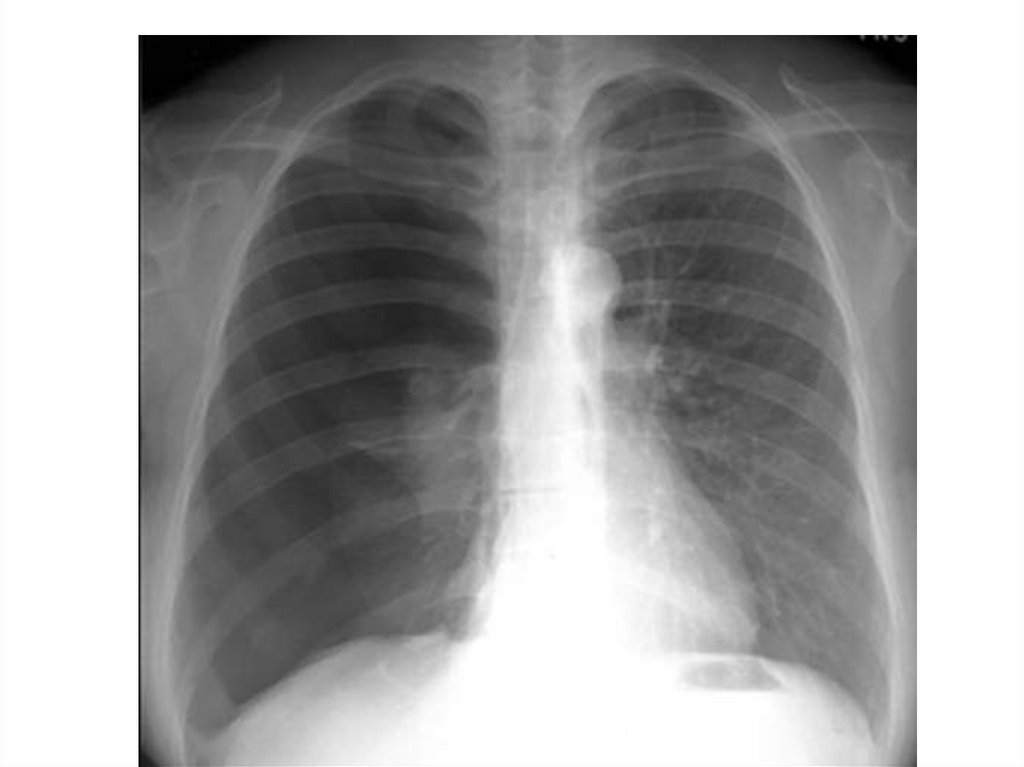

Эмфизема